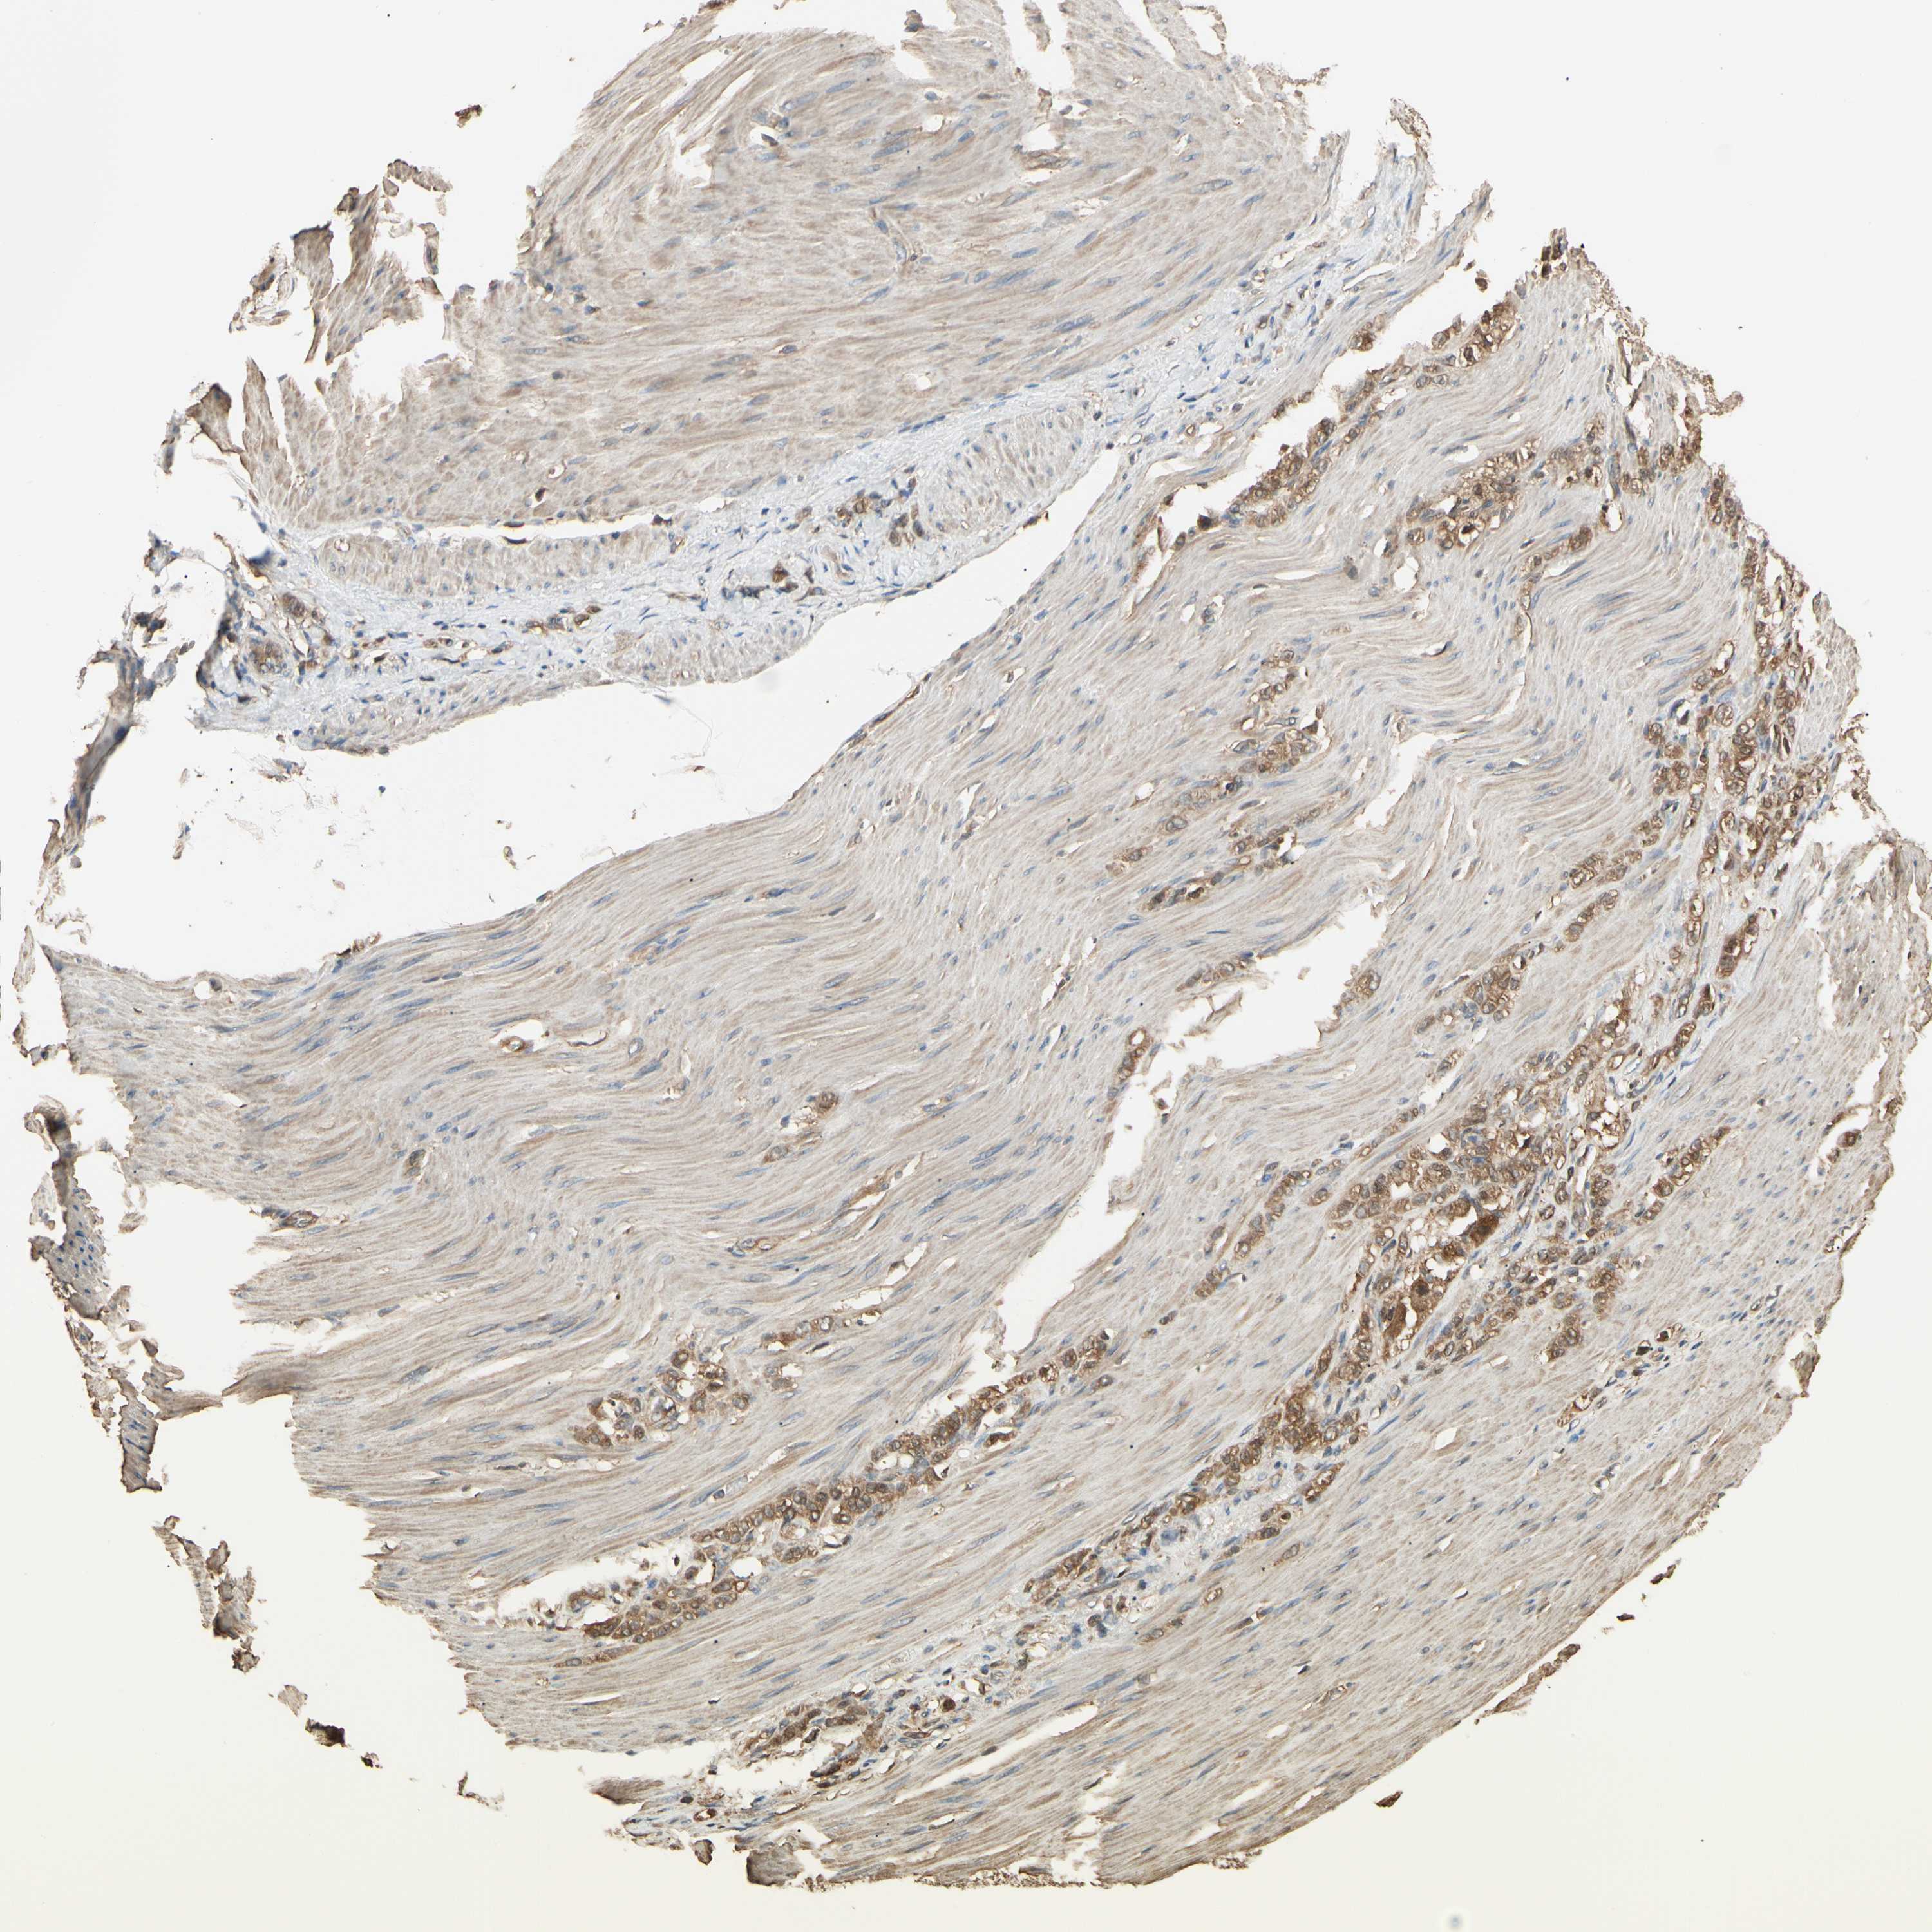

STOMACH CANCER - Protein expressioni

A mouse-over function shows sample information and annotation data. Click on an image to view it in a full screen mode. Samples can be filtered based on level of antibody staining by selecting one or several of the following categories: high, medium, low and not detected. The assay and annotation is described here.

Note that samples used for immunohistochemistry by the Human Protein Atlas do not correspond to samples in the TCGA dataset.

Antibody stainingi

Antibody staining in the annotated cell types in the current human tissue is reported as not detected, low, medium, or high, based on conventional immunohistochemistry profiling in selected tissues. This score is based on the combination of the staining intensity and fraction of stained cells.

Each image is clickable and will lead to virtual microscopy that enables deeper exploration of all samples and also displays staining intensity scores, fraction scores and subcellular localization as well as patient and tissue information for each sample.

Antibody HPA008445

Antibody CAB016200

Antibody CAB021109

Antibody CAB047350

Staining

High

Medium

Low

Not detected

Intensity

Strong

Moderate

Weak

Negative

Quantity

>75%

75%-25%

<25%

None

Location

Nuclear

Cytoplasmic/membranous

Cytoplasmic/membranous,nuclear

Adenocarcinoma, NOS

Adenocarcinoma, High grade